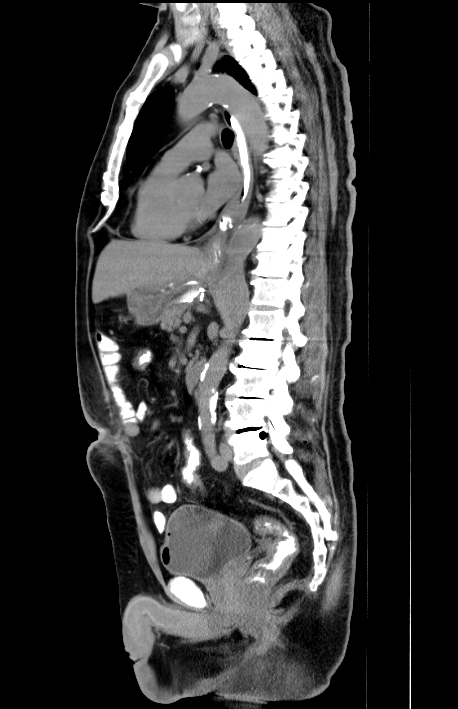

撮影された画像データを⽤いて、様々な⾓度から体を観察できます。よく使われるのは、体を横からみた⽮状断(サジタール画像)、体を正⾯からみた冠状断(コロナール画像)です。また3D画像も作成可能です。⼿術や検査結果の説明に使⽤されています。